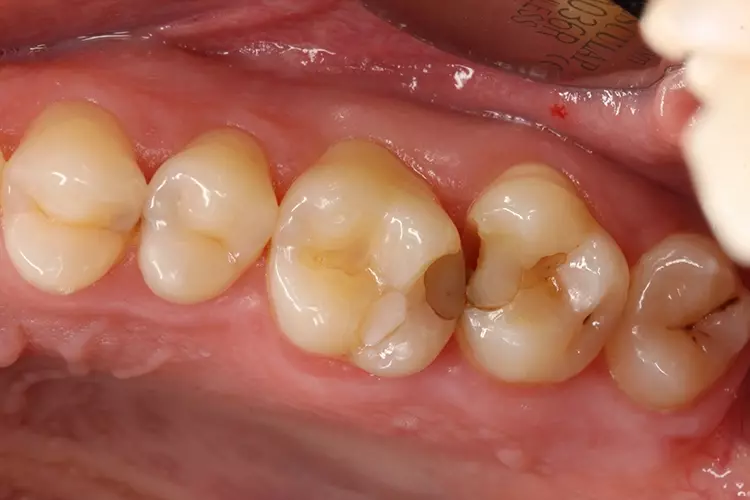

Bei einem 31-jährigen Patienten ohne Vorerkrankungen mussten aufgrund primärer und sekundärer Karies mehrere Seitenzahnfüllungen ersetzt und erneuert werden. Die Zähne 26 und 27 waren mit älteren Kompositfüllungen versorgt.

Die vorhandenen Restaurationen waren defekt und undicht, sodass sich Speisereste einlagerten (Abb. 1). Die Bissflügelaufnahme bestätigte den klinischen Befund (C2). Die Sekundärkaries hatte nur wenig das Dentin infiltriert (Abb. 2).